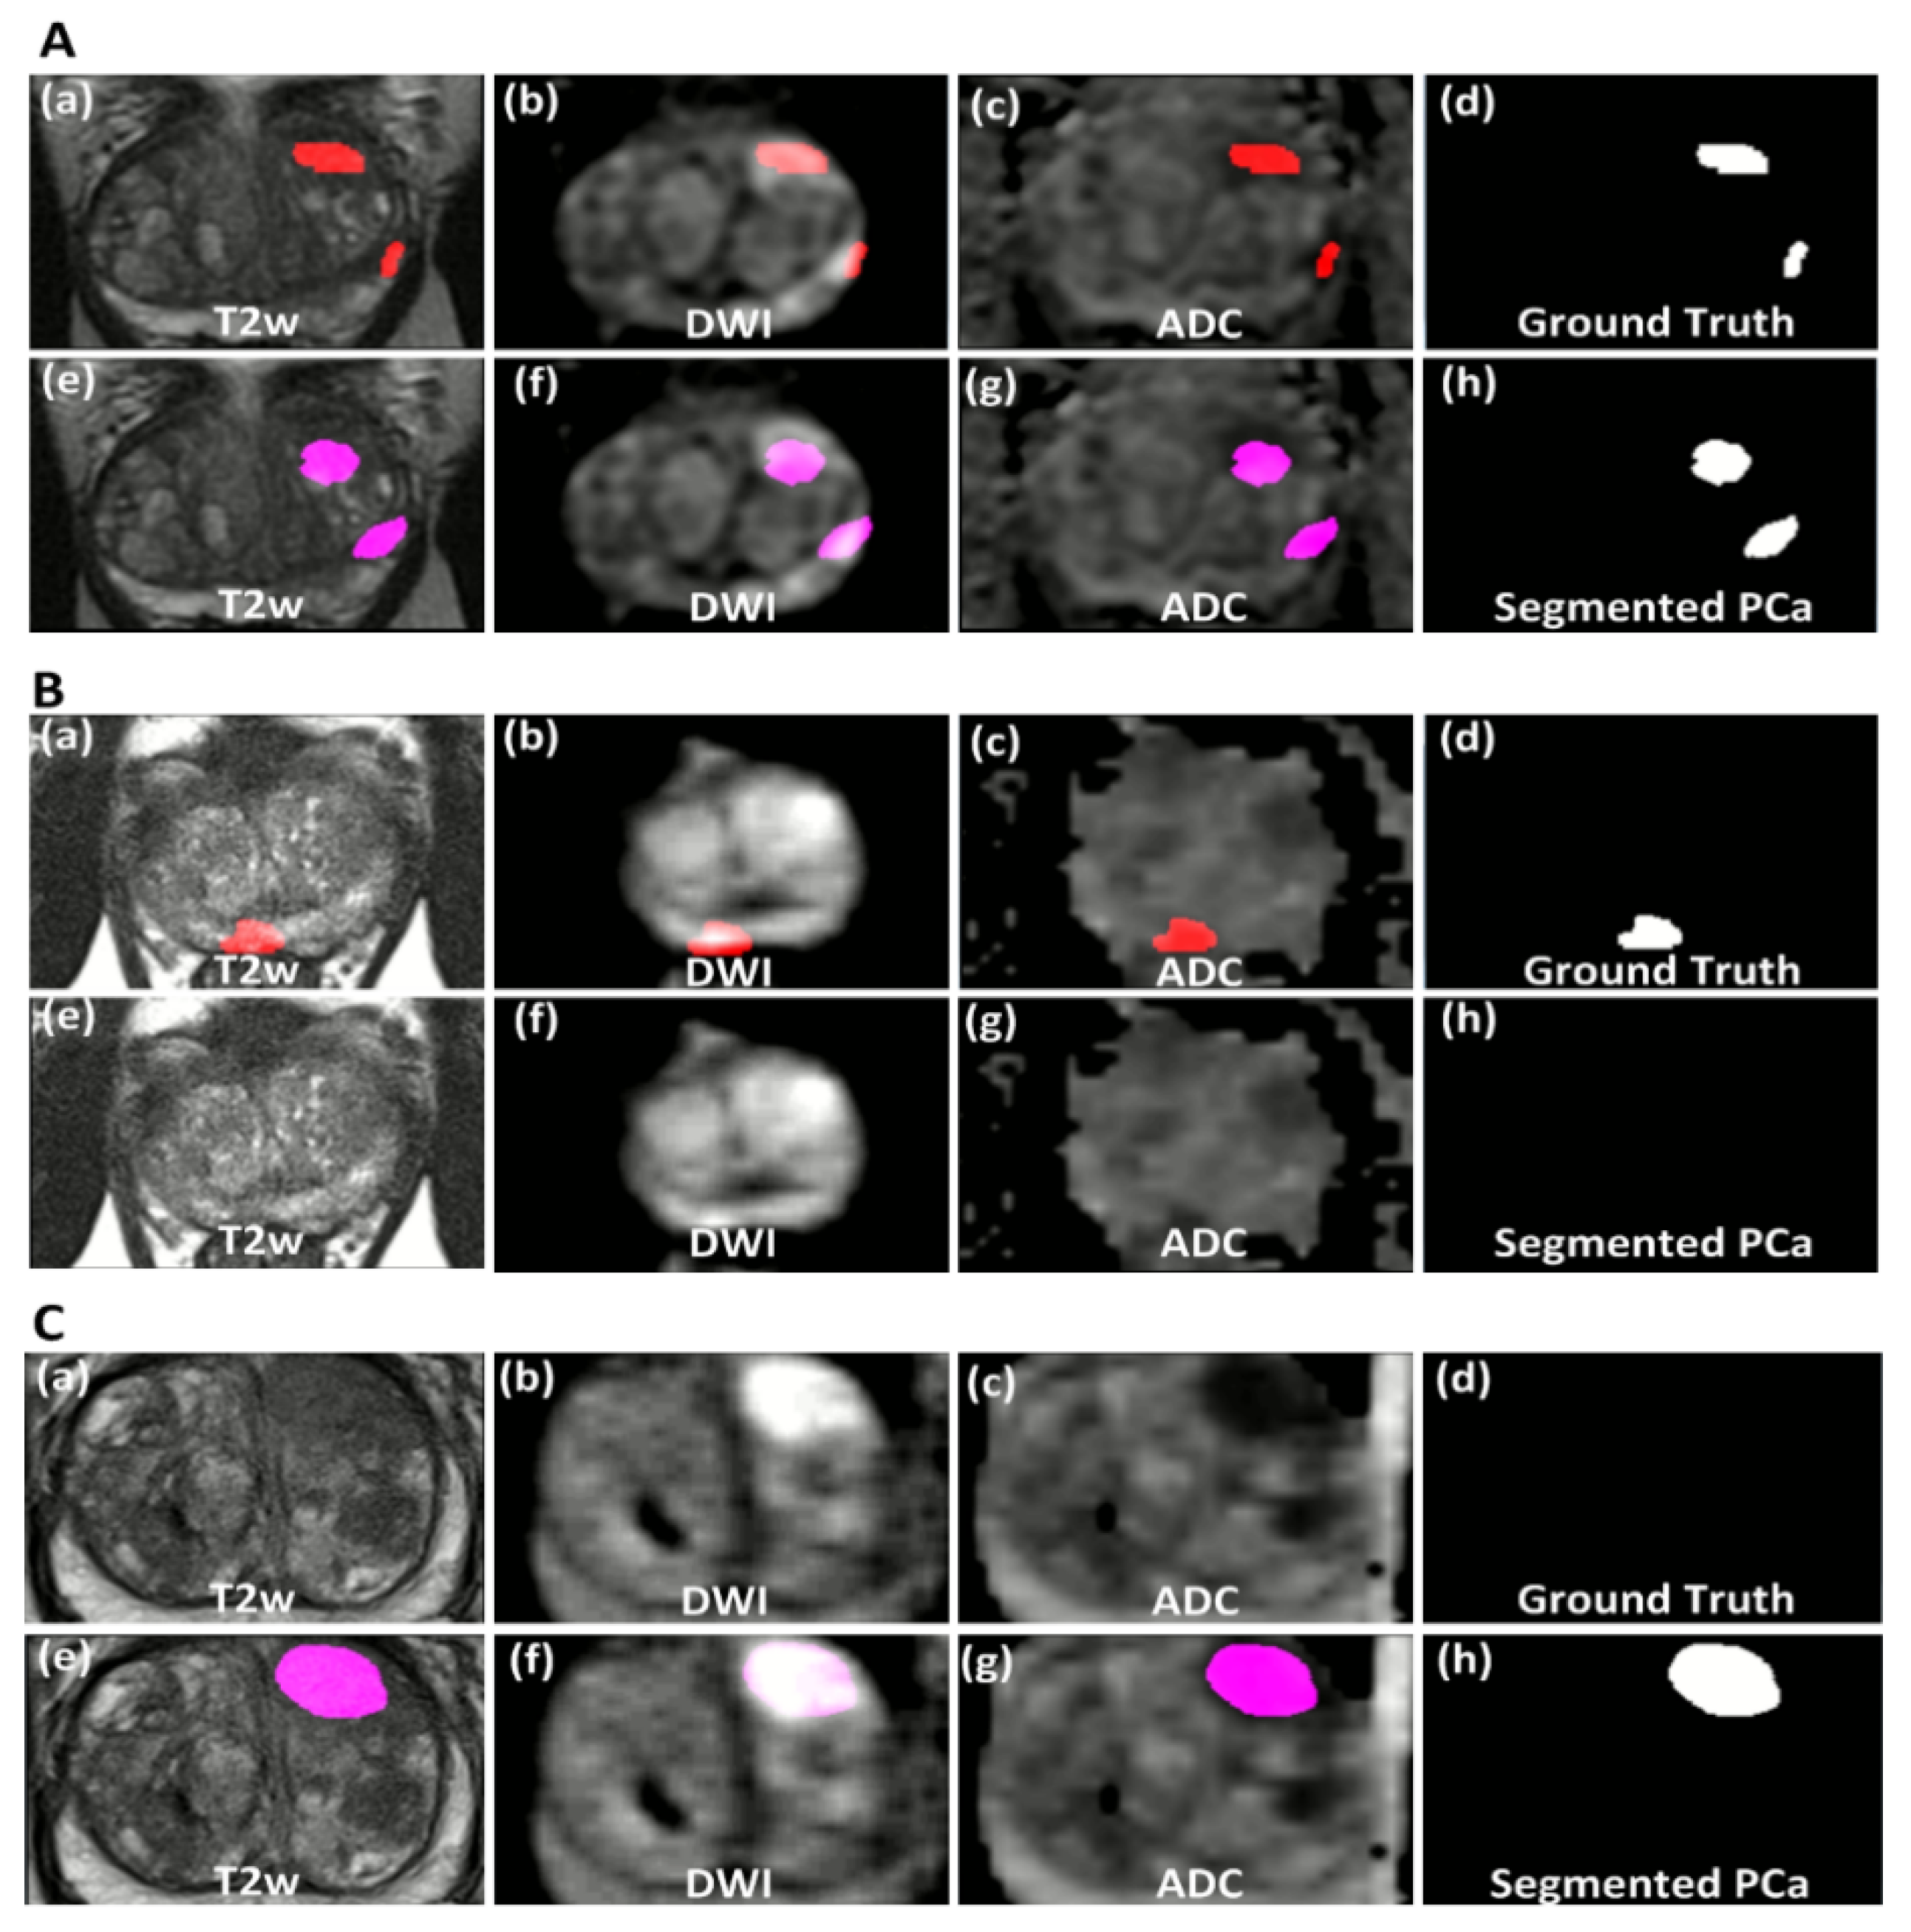

3. Results